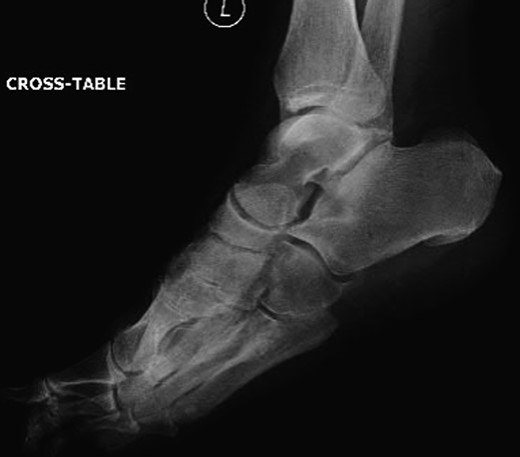

Dorsoplanter, lateral and oblique radiographs demonstrated an additional bone immediately distal to the middle cuneiform articulating with the second metatarsal base and middle cuneiform. Second and third metatarsals were shorßt in comparison with normal (Figs 1–3). Osteoarthritis was seen in all TMTJs and the first MTPJ. A computed tomography (CT) scan confirmed the presence of the additional bone and degenerative joint disease (Figs 4 and 5).

Lateral radiograph of the left foot with the clearly visible additional middle cuneiform.